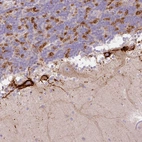

Immunohistochemical staining of human cerebellum shows strong cytoplasmic positivity in a subset of cells.